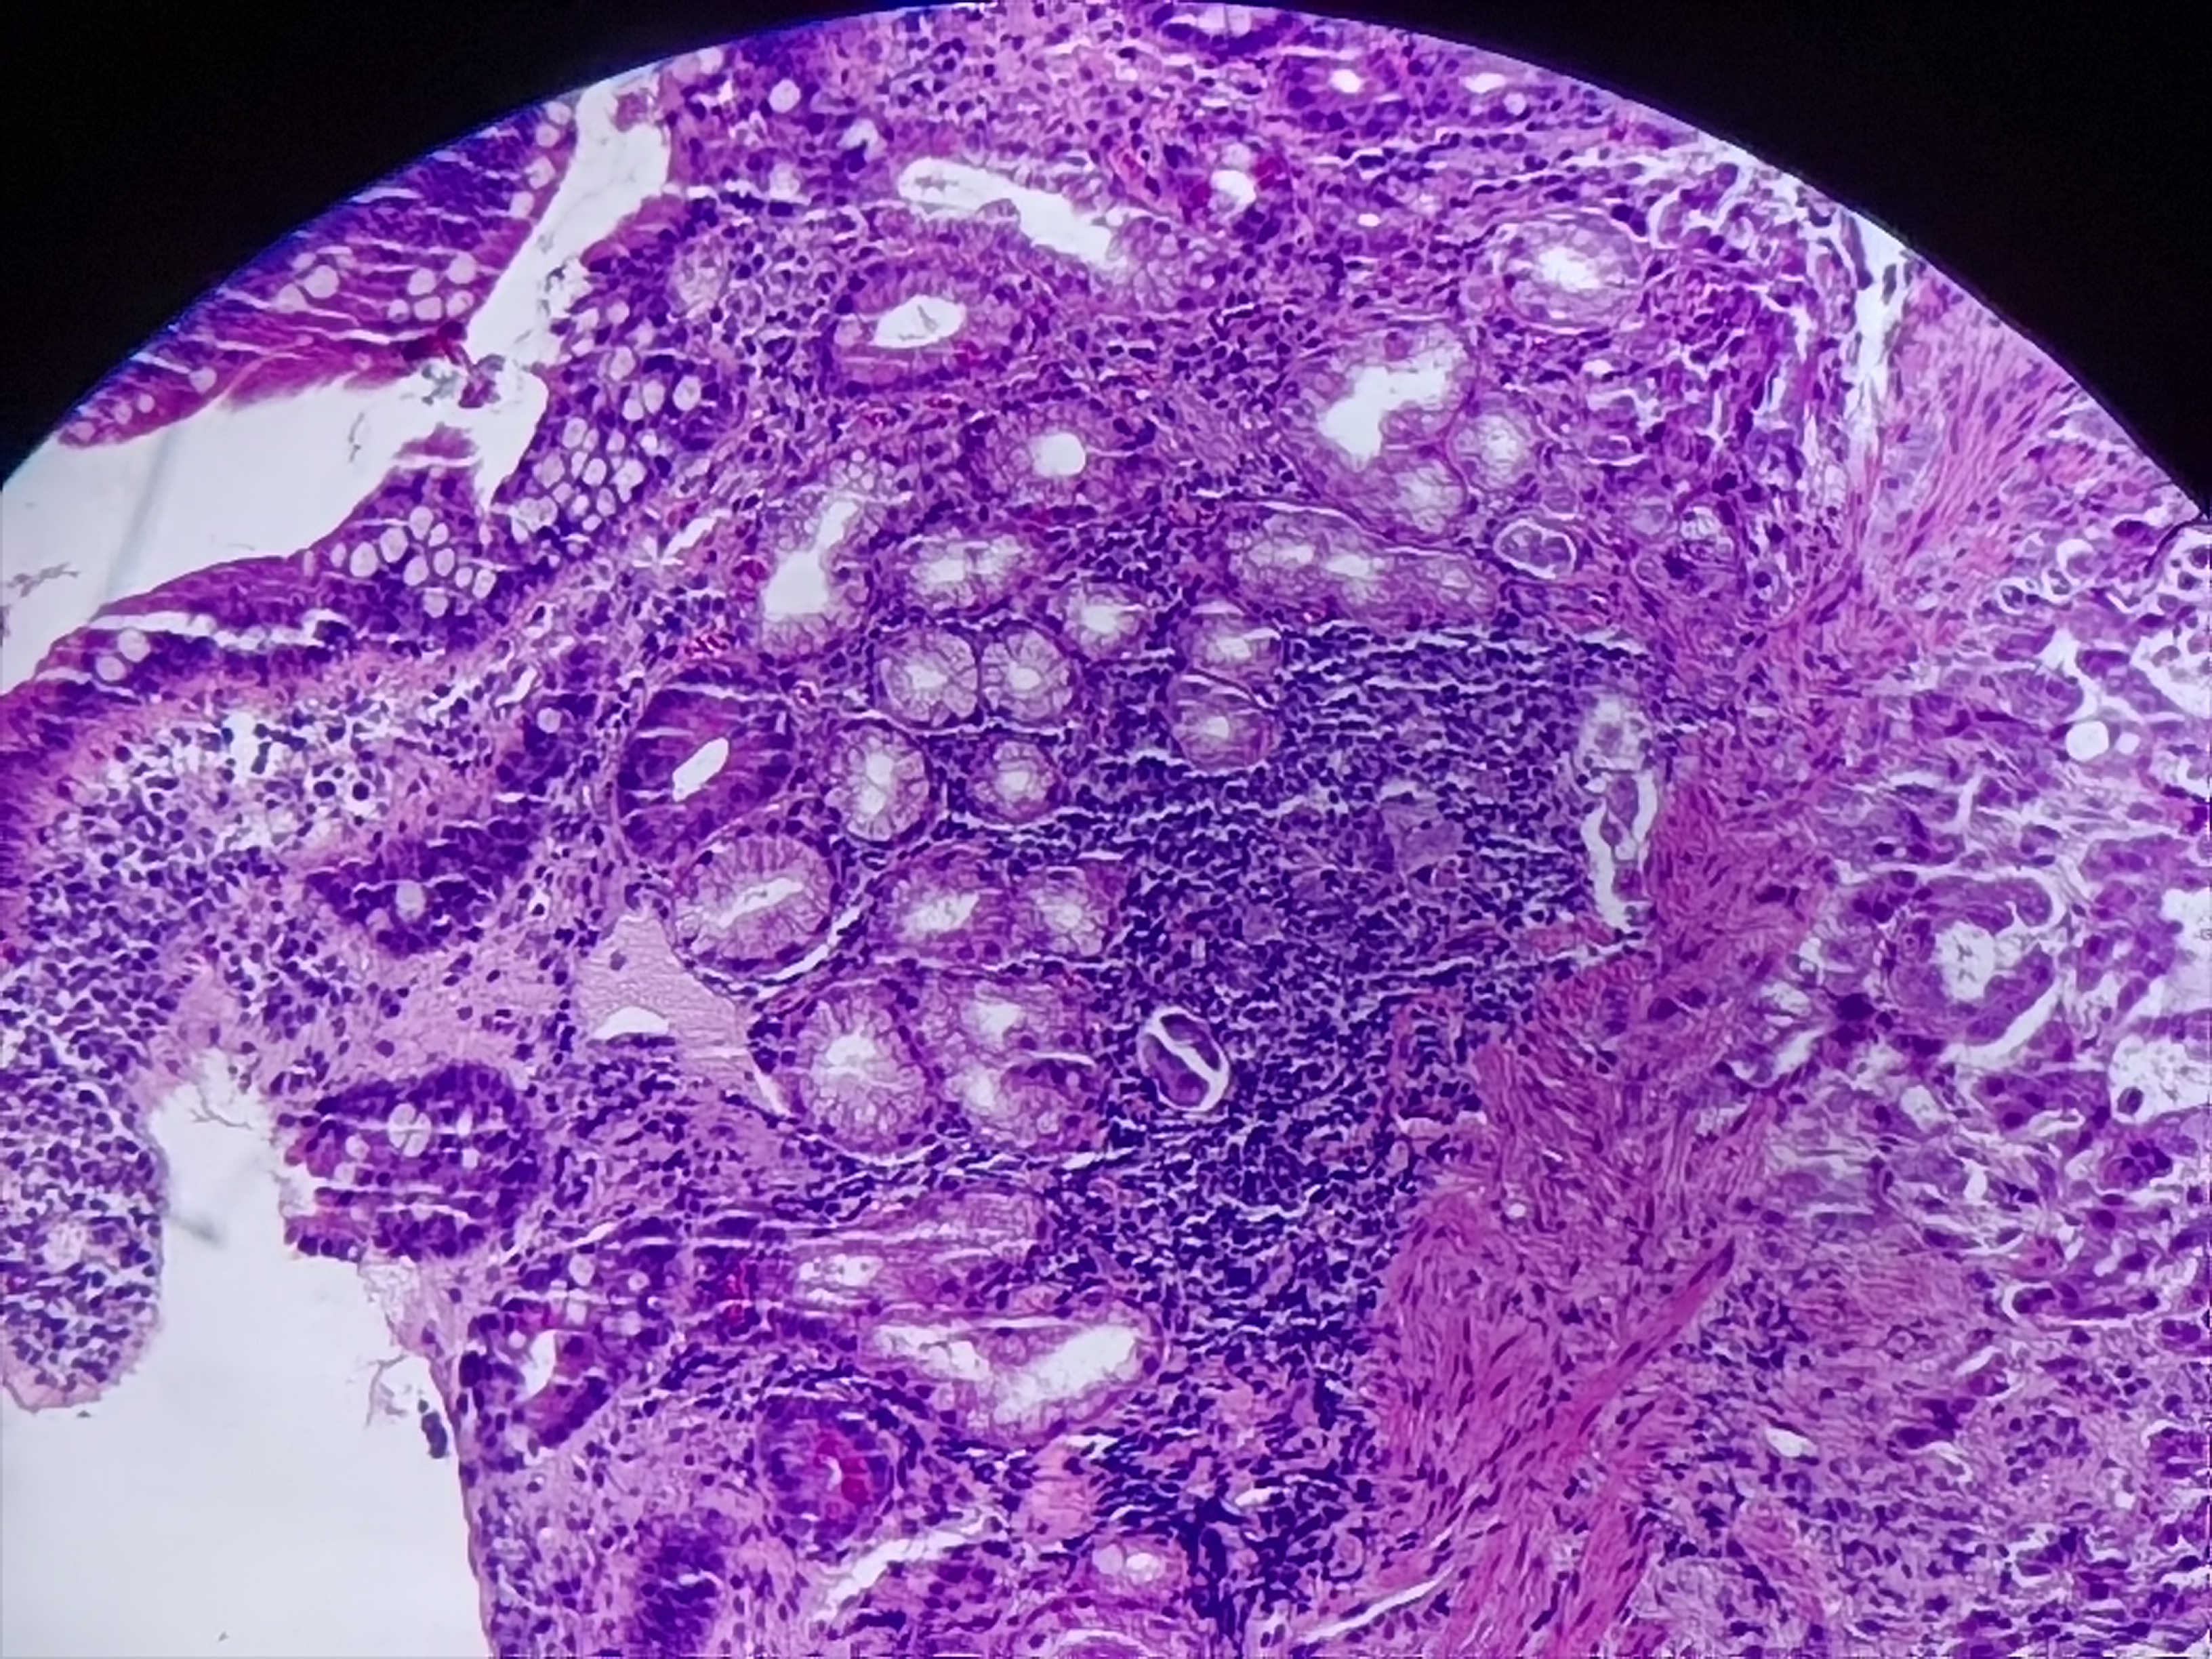

十二指肠球部活检

十二指肠球部可见一大小约0.5*0.6cm隆起性病变

标本名称

十二指肠球部粘膜活检

大体所见

灰白灰红组织1块

异位胰腺组织。